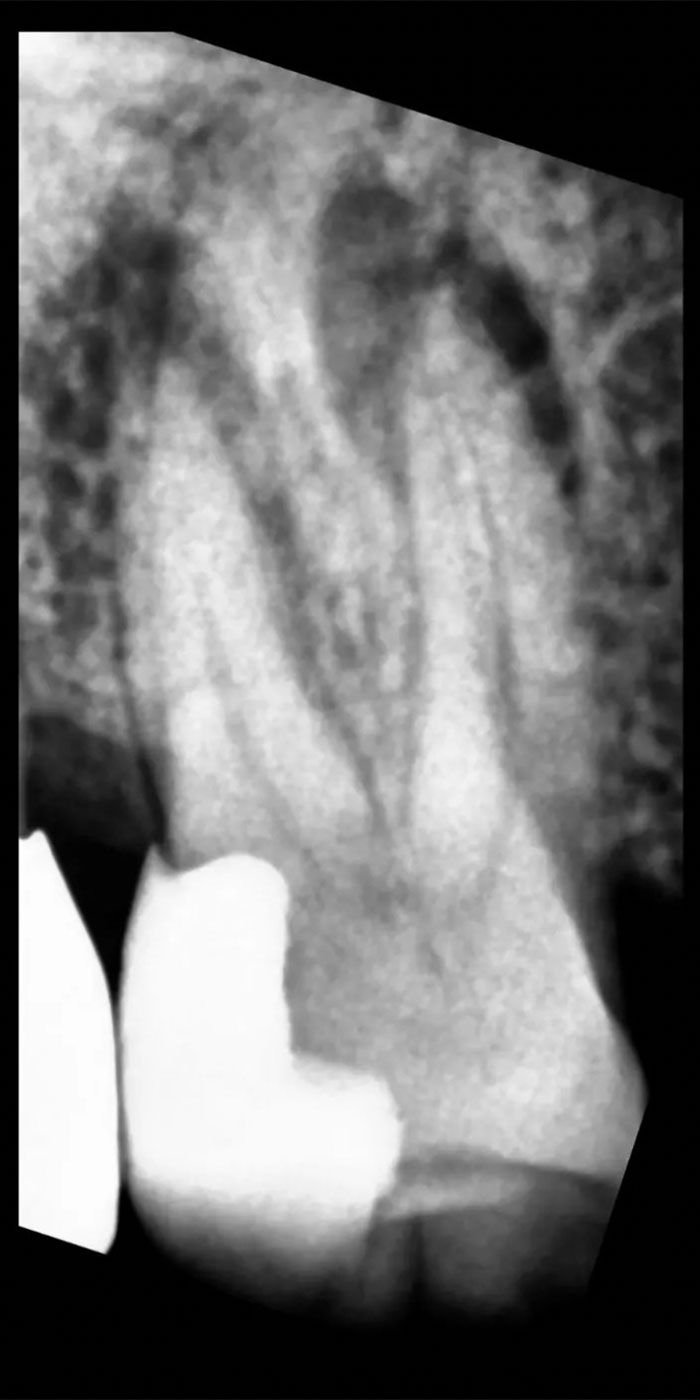

- Our skilled Schenectady root canal dentists will perform a thorough examination and X-rays to assess the extent of damage or infection within the tooth.